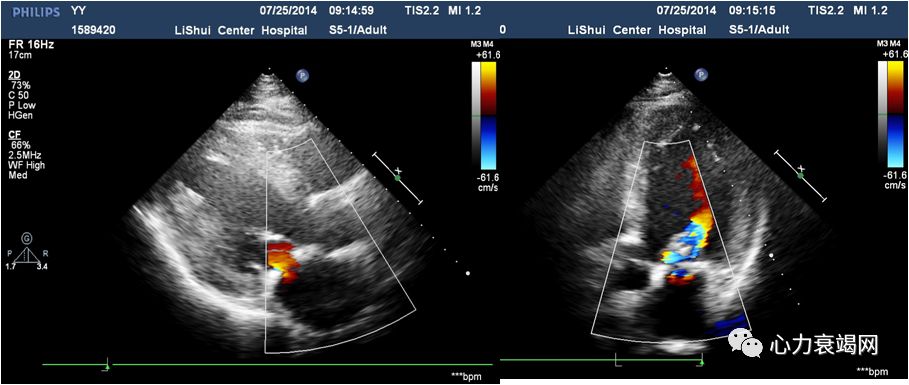

➤ 全心扩大(左房内径48mm,左室内径(d)70mm,(s)53mm)

➤ LVEF48%,肺动脉压80mmHg

➤ 二尖瓣前叶收缩期突向左房,二尖瓣收缩期见中-重度关闭不全

➤ 室间隔厚11mm,左室后壁厚11mm